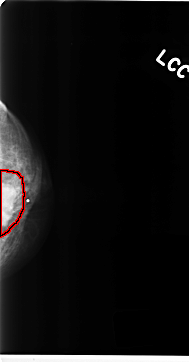

FILE: C_0141_1.LEFT_CC.OVERLAY

TOTAL_ABNORMALITIES 1

ABNORMALITY 1

LESION_TYPE MASS SHAPE IRREGULAR MARGINS MICROLOBULATED

ASSESSMENT 5

SUBTLETY 5

PATHOLOGY MALIGNANT

TOTAL_OUTLINES 1

BOUNDARY